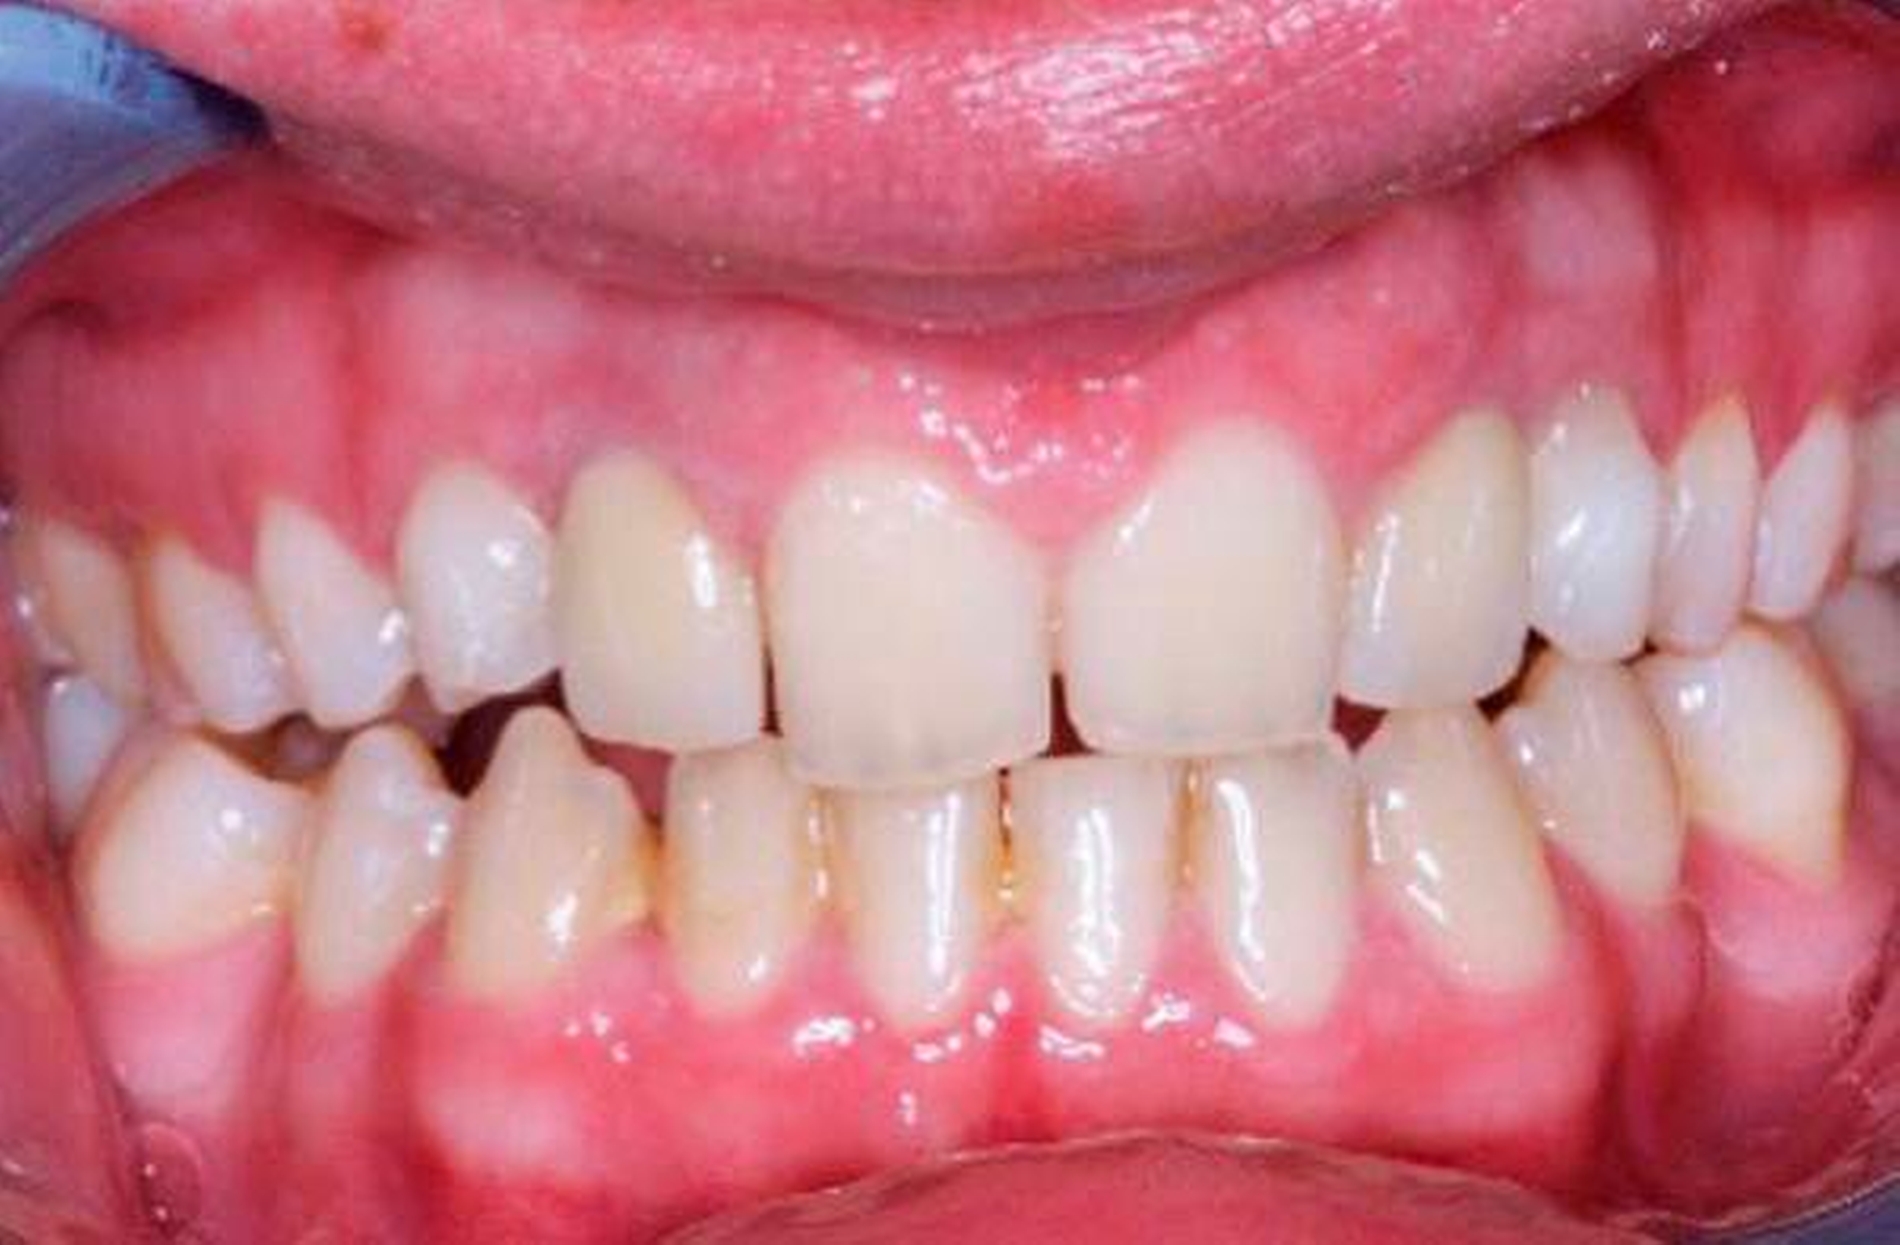

Die zehnjährige Patientin wurde uns von der Kieferorthopädin zur Wertung möglicher chirurgischer Maßnahmen bei insgesamt acht Nichtanlagen (Abbildung 1a bis c) vorgestellt. Im OPG stellt sich das Fehlen von drei permanenten Zähnen im I. Quadranten, von vier im II. Quadranten und einem im III. Quadranten dar (Abbildung 1c). Aufgrund des noch jungen Alters der Patientin zum Zeitpunkt der Erstvorstellung und des damit noch verbundenen Vorhandenseins der Milcheckzähne 73 und 83 entschieden wir uns für das folgende kieferorthopädisch-kieferchirurgische Vorgehen (Abbildung 2):

Im Alter von 17 Jahren, also 5,5 Jahre post transplantationem, sind deutliche Fortschritte der kieferorthopädischen Behandlung mit dem Ziel der Bisshebung erkennbar (Abbildung 6). Um einen vorzeitigen Verlust der Milchzähne durch KFO-Zug zu vermeiden, entschied sich die Kieferorthopädin gegen eine Bewegung der Milchzähne in Position 13, 12, 22 und 23. Die Milchzahntransplantate in Position 12 und 22 weisen jetzt deutliche Zeichen einer apikalen Resorption auf, was bei plötzlichem Verlust die Einleitung implantologischer Maßnahmen zur Folge hätte.

Im Alter von nunmehr 21 Jahren, also elf Jahre nach Milchzahn- und Prämolaren-Transplantation, kam es zu einer klinischen Lockerung der Milchzahn-Transplantate, weswegen unverzüglich eine implantologische Versorgung in regio 12 und 22 eingeleitet wurde. Bei der Extraktion der gelockerten Milchzähne erfolgten alveolarplastische Maßnahmen mit Auffüllung der Extraktionswunden mit Knochenersatzmaterial. Die Implantate wurden acht Wochen nach Alveoloplastik inseriert, die prothetische Versorgung erfolgte 2,5 Monate später (Abbildung 7). Ohne größeren chirurgischen Aufwand konnte ein ästhetisch ansprechendes periimplantäres Lagergewebe geschaffen werden. Die erreichte klinische Bisshebung (Abbildung 7a) kann unter Berücksichtigung des ursprünglichen Fehlens von insgesamt sieben Zähnen im Oberkiefer als sehr zufriedenstellend angesehen werden. Eine weitere Verbesserung der ästhetischen Situation kann im Rahmen der noch notwendig werdenden implantologisch-prothetischen Versorgung erfolgen.